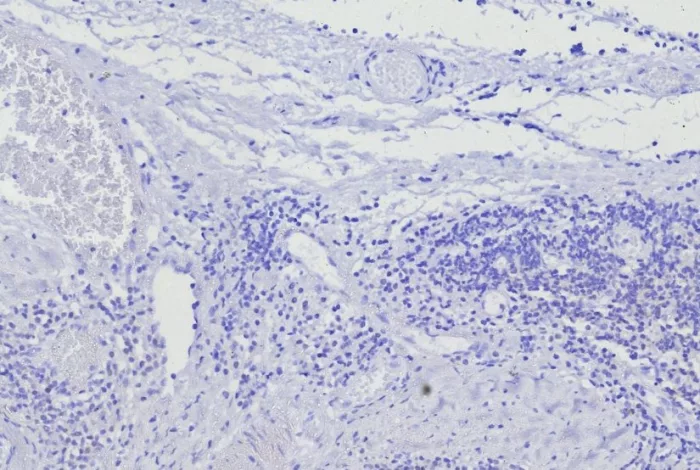

Formalin-fixed, paraffin-embedded human tonsil stained with BOB1 Mouse Monoclonal Antibody (BOB1/7469). HIER: Tris/EDTA, pH9.0, 45min. 2°C: HRP-polymer, 30min. DAB, 5min.

BOB.1 expression in a variety of established B-cell lines, representing different stages of B-cell development, has suggested a constitutive, B-cell-specific expression pattern. LP cells in nodular lymphocyte predominant Hodgkin lymphoma, because they are germinal center-derived, are consistently immuno-positive for BOB.1. Conversely, only some cases of classical Hodgkin lymphoma show BOB.1 immuno-reactivity within the Hodgkin and Reed-Sternberg cells. �Expression of BOB.1 has been reported in follicular center cell lymphoma, diffuse large B-cell lymphoma and some cases of acute myeloid leukemia. �B-CLL, marginal zone lymphoma, and mantle cell lymphoma may show weak to moderate immunoreactivity.